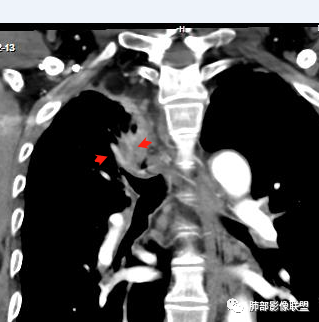

内部支气管近端狭窄,远端粘液栓

内部血管也通畅

不踏实的是这里稍膨隆

恶性待排吧

结合本病例,老年男性患者,慢性病程,急性加重,无吸烟史,影像学表现为右肺上叶尖后段斑片实变密度影,整体边界清晰,边缘平直收缩为主,周边散在纤维条索影,内部见支气管内粘液栓,血管影走形正常,没有明显破坏,增强扫描明显强化,缺乏典型分叶毛刺、胸膜改变,病灶也未显示清楚的磨玻璃勾边,病灶大而肺门纵隔未见肿大淋巴结,综合考虑慢性炎性肉芽肿可能性大。但恶性,结核能完全排除吗?我想对临床医生来说还是有很大考验的。